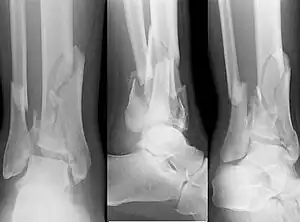

X-ray of a fracture involving the articular surface of the Tibia

A pilon fracture, is a fracture of the distal part of the tibia, involving its articular surface at the ankle joint. Pilon fractures are caused by rotational or axial forces, mostly as a result of falls from a height or motor vehicle accidents. Pilon fractures are rare, comprising 3 to 10 percent of all fractures of the tibia and 1 percent of all lower extremity fractures, but they involve a large part of the weight-bearing surface of the tibia in the ankle joint. Because of this, they may be difficult to fixate and are historically associated with high rates of complications and poor outcome.[1][2][3][4]